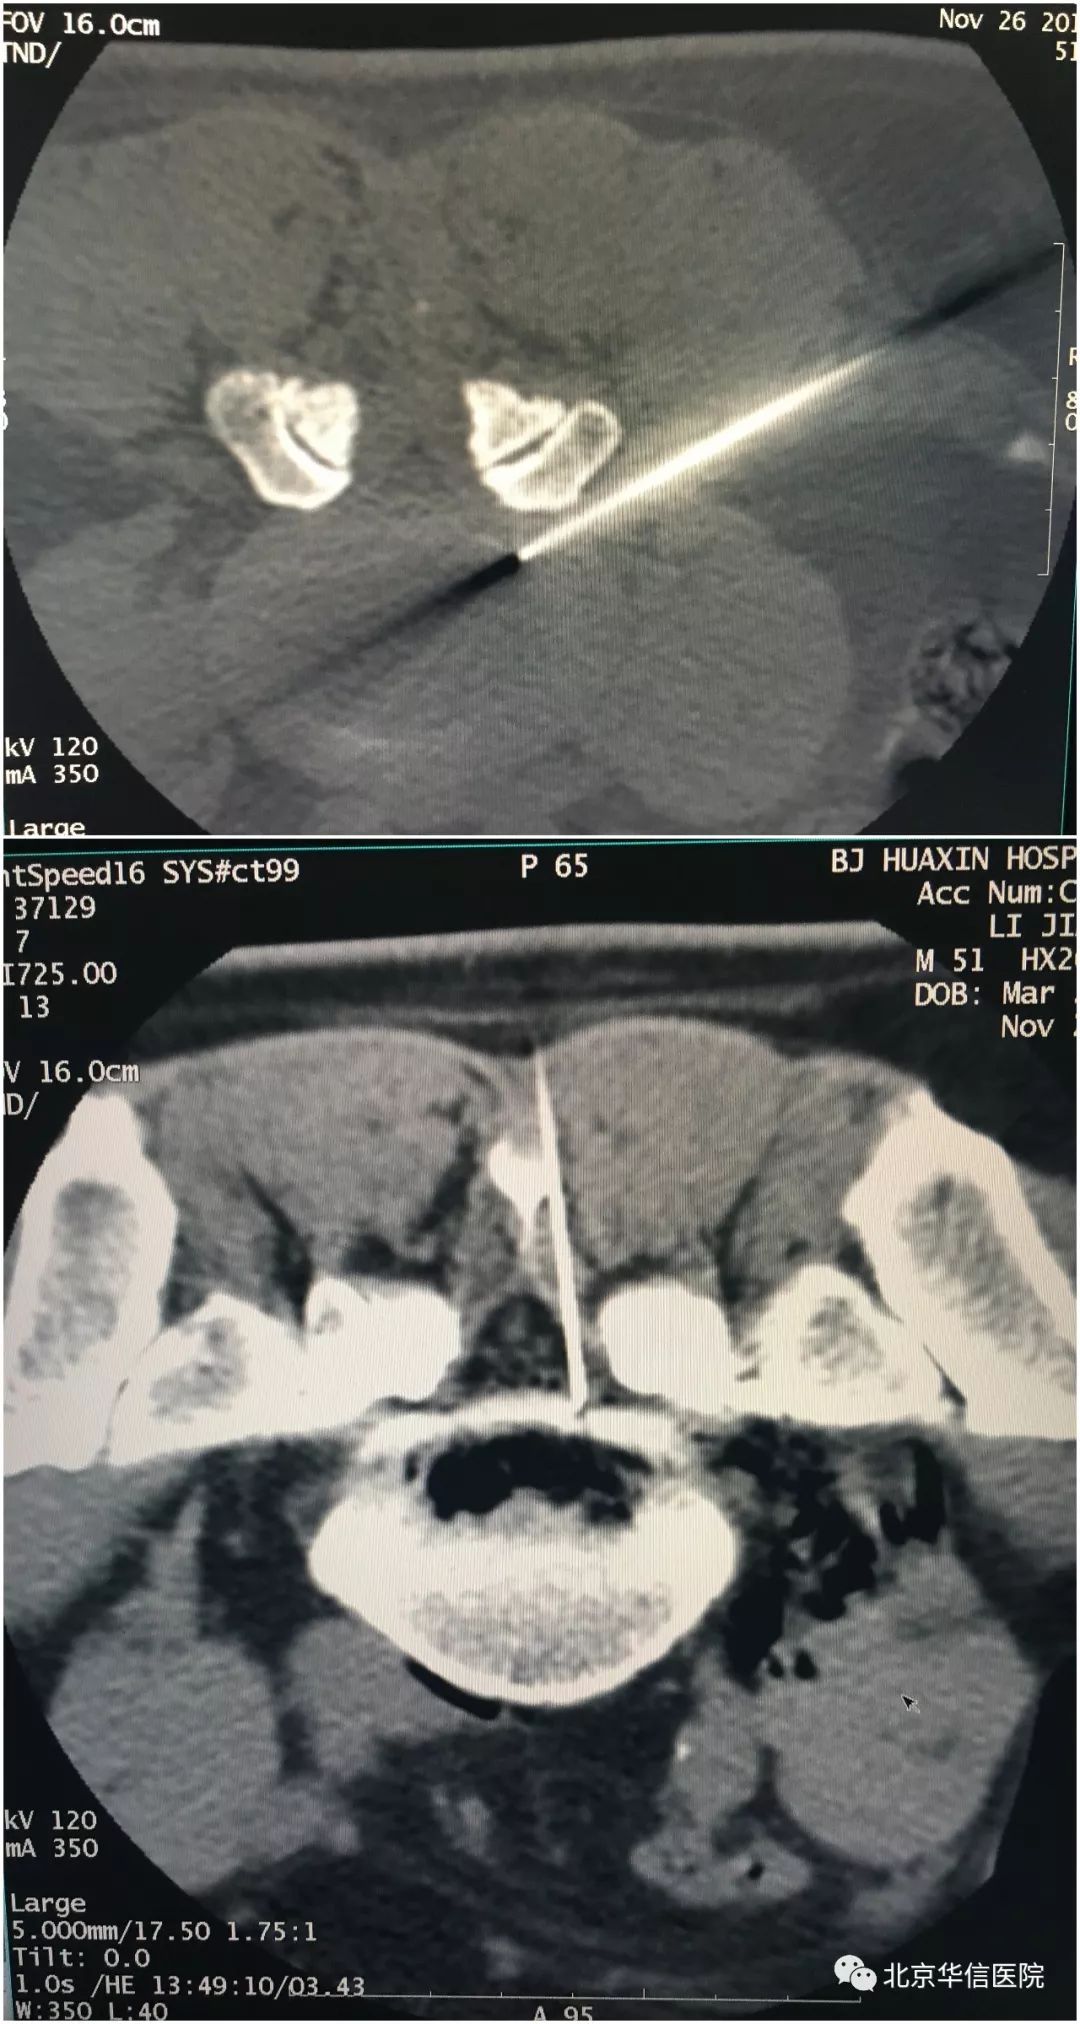

吴先生住院后,完善了手术前的相关检查。在各项指标允许接受手术的情况下,麻醉科关圆、庞晓林两位医生在CT室杨毅医生的配合下,顺利为患者进行了腰椎间盘低温等离子和椎间盘臭氧注射的微创手术。整个手术没有切口,只有一个针眼,创伤很小。手术过程也十分顺利,仅耗时40分钟,患者全程无痛苦。在手术结束当天,吴老先生腰部及腿部的疼痛就明显缓解了,下肢感到前所未有的轻松。吴先生感激地说道:“太神奇了!你们真是我的救星啊!”

穿刺针在CT引导下进入病变的椎间盘靶点